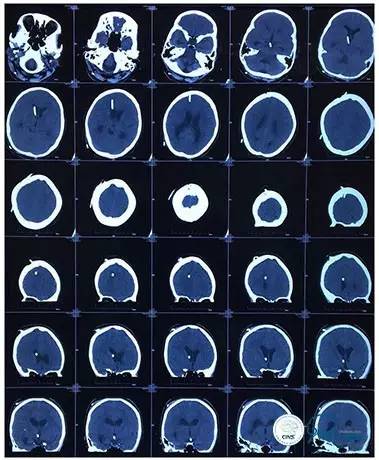

2016-06-03 CT

2017-06-07 CT

术后头颅CT

复查头颅及颞骨CT未见明显异常。

头颅CT(2017.6.20)

颞骨CT(2017.6.20)